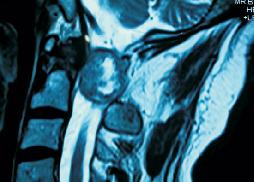

Large CV Junction Intradural Tumor